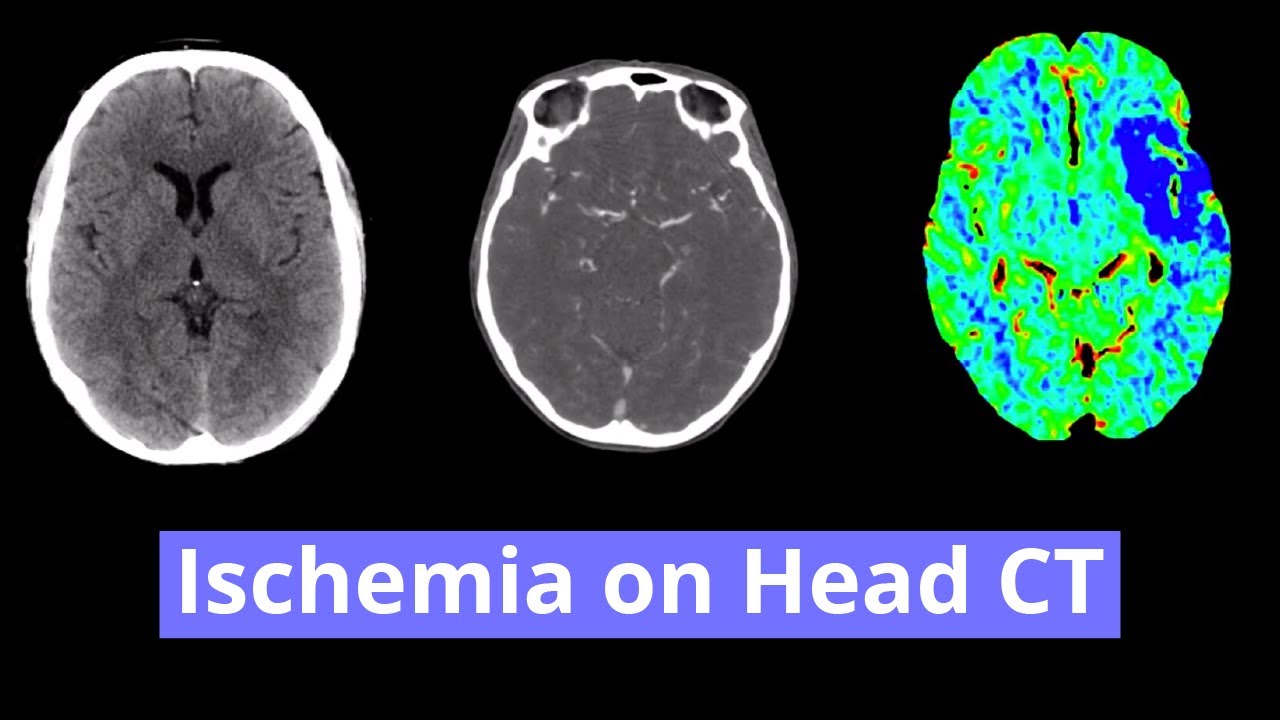

- Hypodensity with loss of gray-white differentiation in the right PCA territory, including the right occipital lobe and ventrolateral right thalamus

- Right PCA territory infarct

Hypodensity and loss of gray-white differentiation in the right occipital lobe concerning for acute/early subacute ischemia. Hypodensity in the ventrolateral right thalamus represents age-indeterminate ischemia. Both of these areas are in the right PCA territory. MRI could further assess the extent of ischemia.

No mass effect or evidence of hemorrhagic transformation.